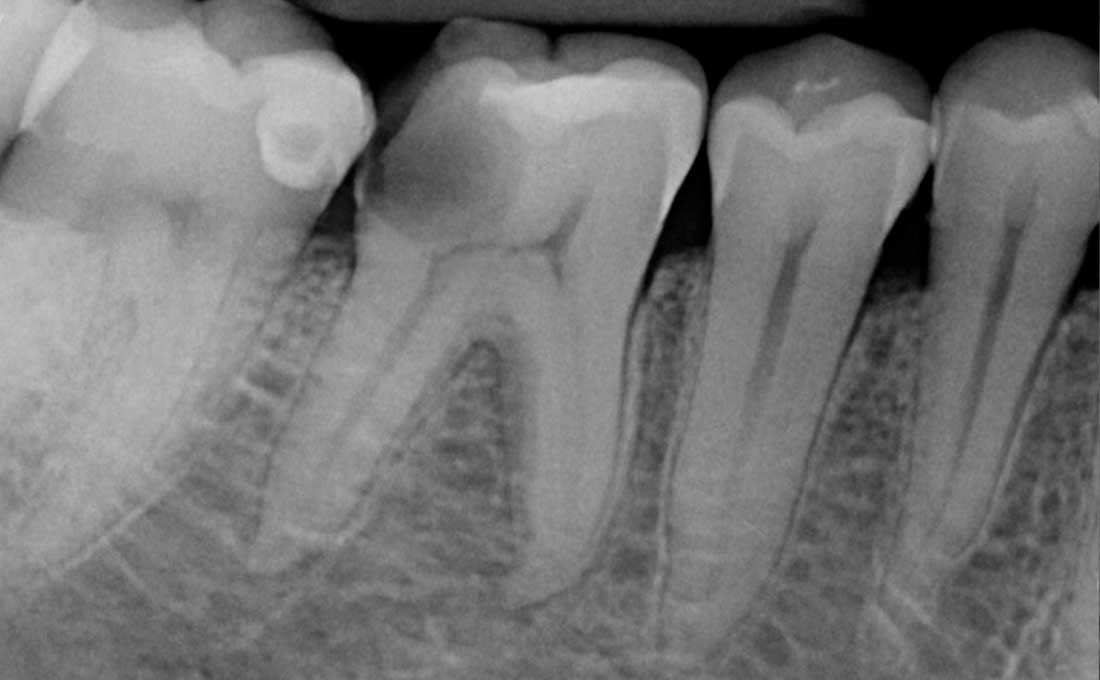

Si parla di trattamento endodontico o di devitalizzazione quando si interviene eliminando la polpa dentaria infiammata e infetta andandola a sostituire dopo un’adeguata disinfezione con materiali da otturazione.

Questa prevede dopo una piccola anestesia locale l’eliminazione di tutto il tessuto dentario affetto dalla carie, l’apertura della camera pulpare e l’eliminazione della polpa dentaria.

Successivamente si procede con la detersione dei canali radicolari e alla loro pulizia tramite strumenti meccanici, in modo da preparare il dente all’otturazione radicolare e alla ricostruzione definitiva.